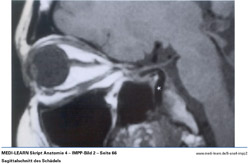

• Sagittalschnitt des Schädels